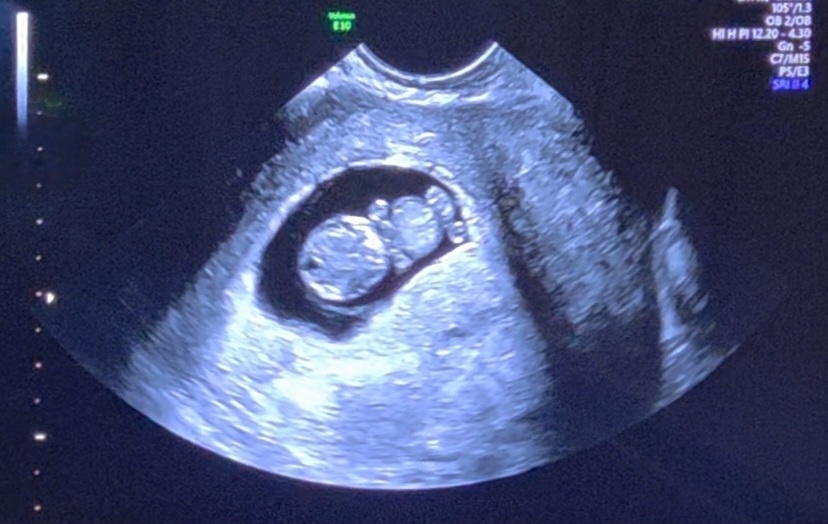

젤리곰 초음파 보구왔어요

9주3일차 오늘 초음파 보구왔어요! 젤리곰이랑 비슷한가요? 앙증맞은 팔과 다리 >.< 하도 꼬물거려서 초음파보는데 선생님이 아기가 잘 움직인다고 하시니 안심 되써요 근데 집에와서 사진을 자세히 보니까 머리에 까만부분이 뇌 라는데 너무 작아보이네요.. 원래 그런건지.. 다시 걱정이되요..ㅠㅠ